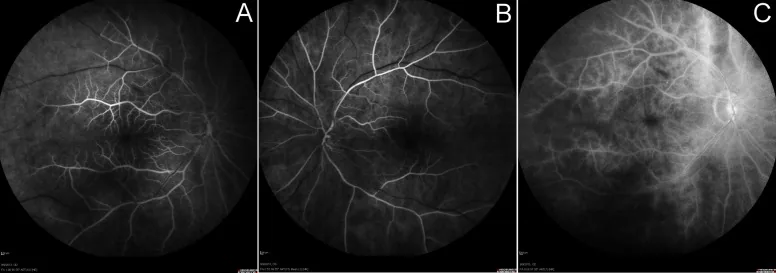

Shemesh E, Karkabi B, Zissman K. Multimodality imaging in subclavian steal syndrome. Oxford medical case reports. 2021;2021(7):omab048. doi:10.1093/omcr/omab048. PMID:34306715; PMCID:PMC8297644.